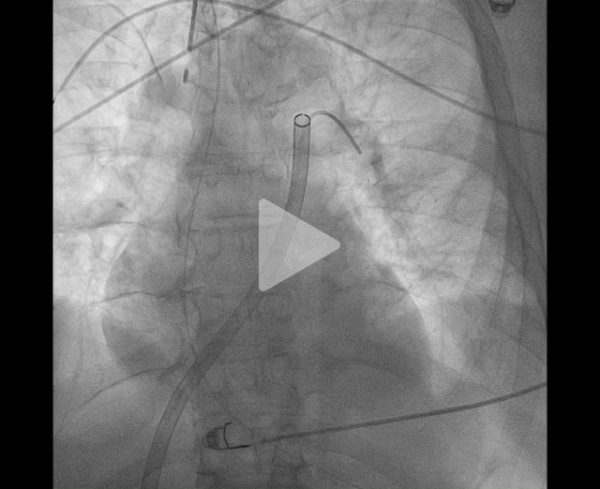

La procédure peut être complétée de l’utilisation de disques intra-artériels pour fragmenter le thrombus et faciliter son aspiration (Figure 9, Vidéos 5, 6 et 7).

Vidéo 5 : angiographie sélective

Vidéo 6 : disques mis en place en aval du thrombus

Vidéo 7 : retrait des disques